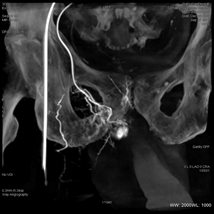

治疗方案及结果: 为了进一步详细观察病灶形态和大小,行3DCT采集,仅需5秒即可完成血管的三维扫描。

3DCT扫描后可在AW工作站中自动重建,可从冠状位、横断位、矢状位多角度观察前列腺。增强扫描可见前列腺组织明显强化,以此推断超选的动脉为PA。

3DCT扫描重建后前列腺动脉清晰可见   术后3DCT扫描见栓塞良好